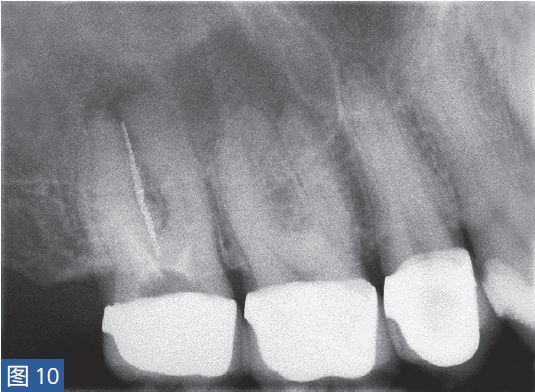

慢性根尖周脓肿(CAA chronic apical abscess)慢性根尖周脓肿(图10和11)是由长期持续的炎症引起的。脓液穿通骨和口腔黏膜,并通过口腔黏膜或上皮的瘘管流出。这些通到表皮的瘘管通常可能作为皮肤损伤而被错误处置。此外,瘘管也可能存在于牙周并通过龈沟引流。瘘管可以部分或完全地被上皮所包绕,这些上皮又被炎性结缔组织包围。临床诊断显示牙髓电活力测试结果为阴性。除非瘘管闭合,否则叩诊和触诊通常都不会引起疼痛。放射学检查,根尖周组织表现从无变化到发生明显变化。

图10:17 牙齿CAA。术前放射学检查,利用牙胶尖显示瘘管。患者因17 牙齿局部瘘管而前来就诊,诉无特殊临床症状。